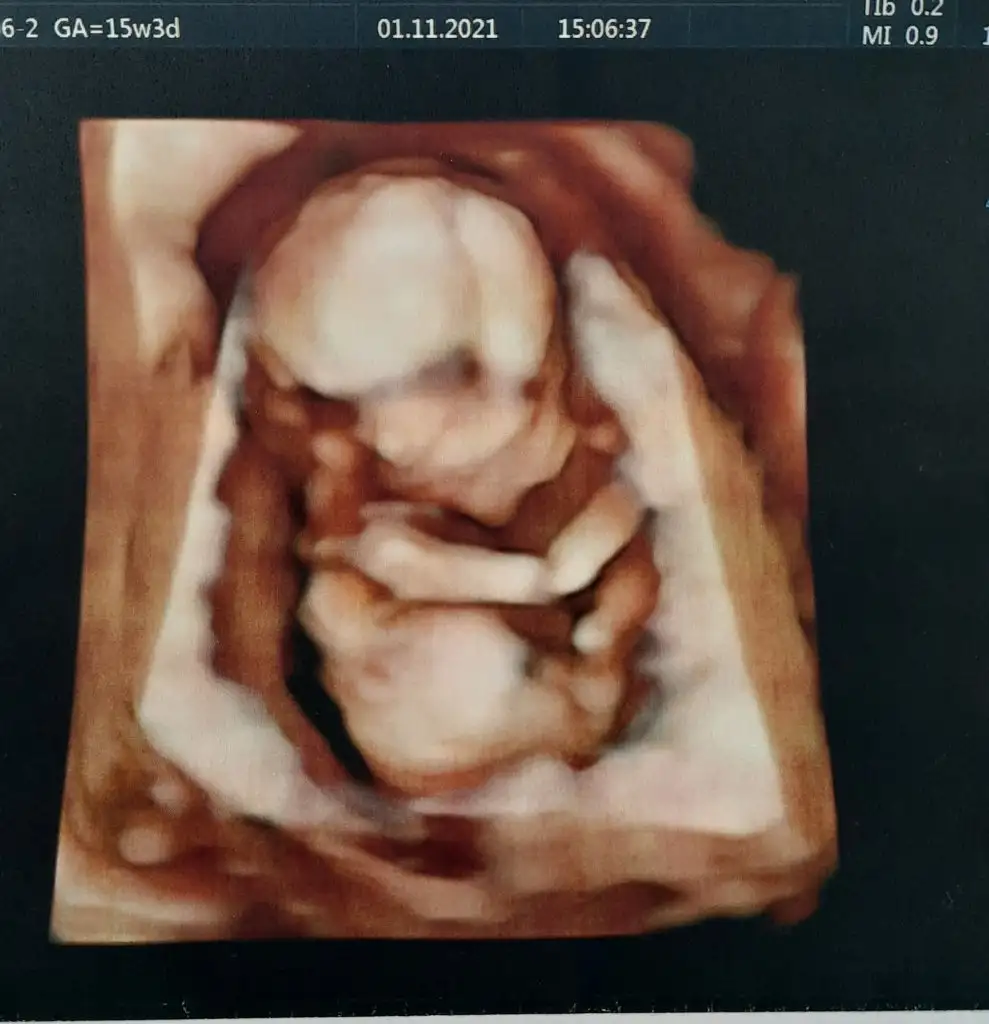

Şimdiye kadar çok net bir görüntü alamadı hiç göbeğimdeki yağ tabakasından dolayı😅

ama dün yakaladı bir poz yandan da olsa😍 yüzünü göstermedi sıpa 🙈 detaylıda görürüm inşallah ben de haftaya 🙏

Ay onun arkası dönük kolu mu o 😍 küçücük bi de kulak mi görüyorum sanki 😍😍

Anaaam eli uzunde ovusturuyir sanki uyanamamis beyfendi 😇👼

Birde baya cabuk buyuyolar ki baksana ilk fotograf 15+3, ikincisi 17haftalikken. Yani dusunuyorum 3 aralikta tam 20 hafta olacak, ne kadar buyumustur Allah bilir 😍 17 haftalikkrn bildigin bal yanak 😋

Aynen canım yandan yakaladı 😍 o kulağa bittim zaten minnacık bişey 🥺

354 gram ama işte kulağı kolu ne bilim ya minik bi adam resmen 😍🙏🧿